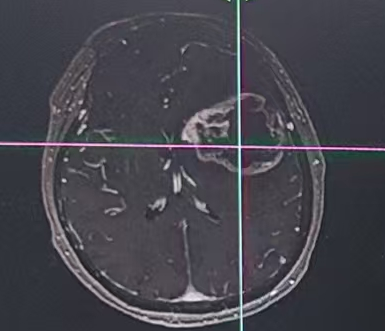

在河北省人民医院,一位63岁女性患者正面临 “生死时速” 的考验。患者因 “右上肢肌力下降伴部分失语5天,加重1天” 入院,病情进展较快——入院仅1天便完全失语,偏瘫症状进一步加重。两院专家联合评估,制定个性化手术方案。

术中利用导航、超吸、电生理等辅助手段,王虎主任成功将肿瘤全部切除,术后患者症状得到明显改善。